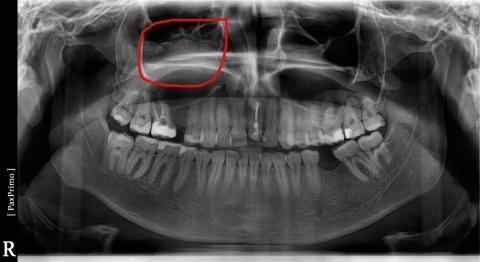

Dobrý deň. čera som absolvoval OPG rontgen a všimol som si na jednej strane dutín že tam je niečo čo na tej druhej strane není. Viete mi povdať o čo sa môže jednať ?Ďakujem.

Dobrý den, jde o stíny, které mohly vzniknout např. přechozeným zánětem dutin. Je to častý vedlejší nález na OPG.